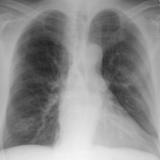

Normal pericardium